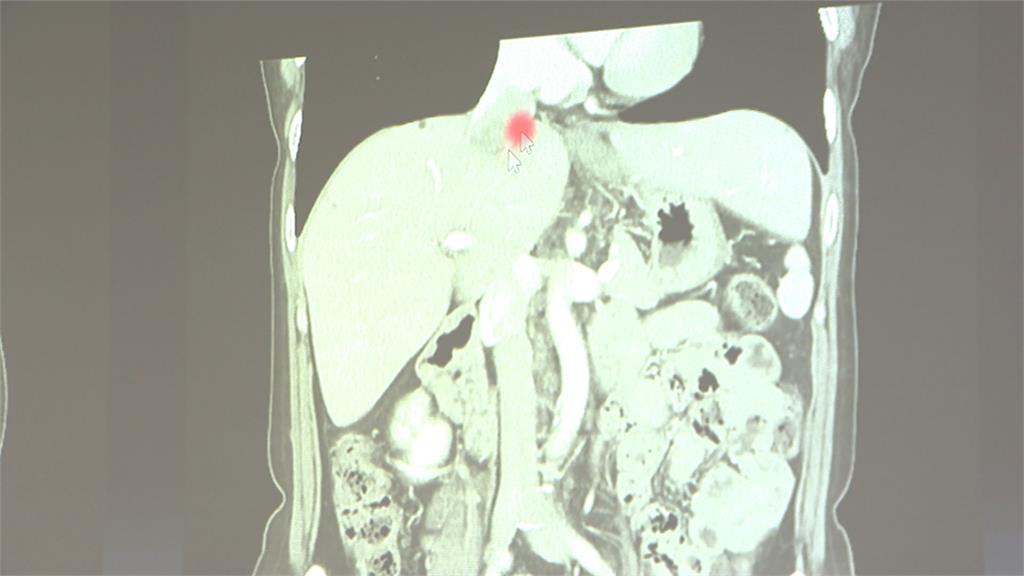

53歲的潘小姐,去年健檢時,發現肝臟有腫塊,進一步確診是惡性平滑肌肉瘤,生長位置一路延伸到進右心房,聽到這消息,讓她十分絕望。

在醫生的鼓勵下,潘小姐沒有放棄,透過肝臟移植科、心臟科、整形外科等,各科醫師強強聯手,將整個肝臟取出,在體外把腫瘤切乾淨,再放回,歷經14個小時,全神貫注,一分一秒都不馬虎,堪稱「拆彈級」手術。